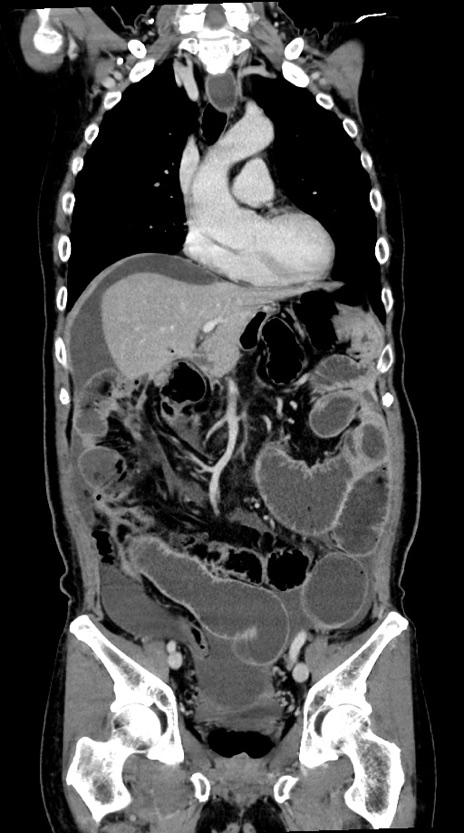

症例28(冠状断像)

【症例】60歳代男性

【主訴】嘔吐

【現病歴】胃癌にて胃全摘後。食思不振が悪化し、夜中に嘔吐することがある。

【既往歴】胃癌、胃全摘、脾摘、胆摘後

【データ】WBC 5900、CRP 10.56